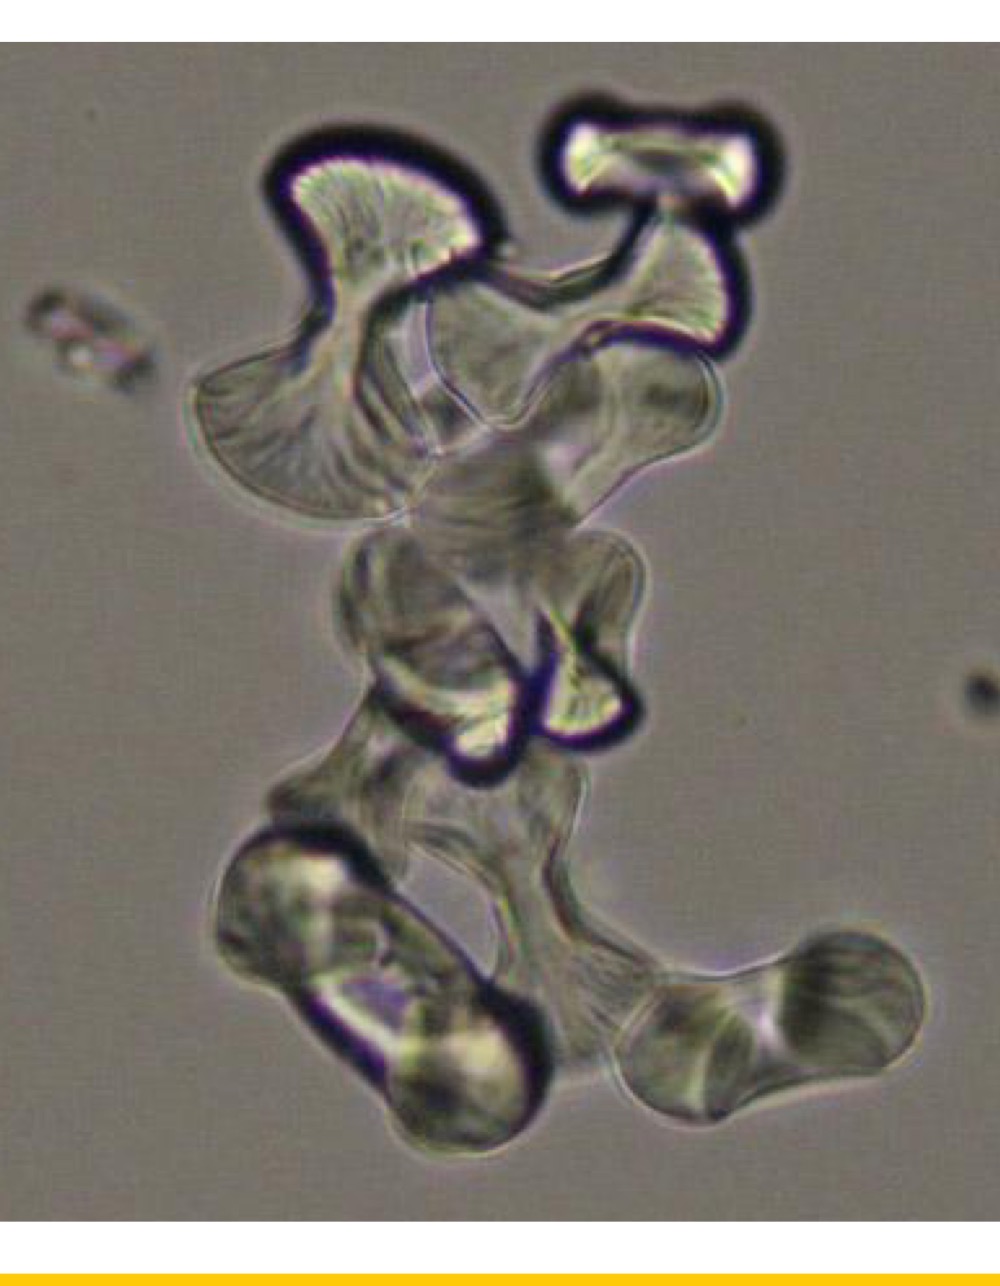

Identify this parasite.

Trichophyton Mentagrophytes